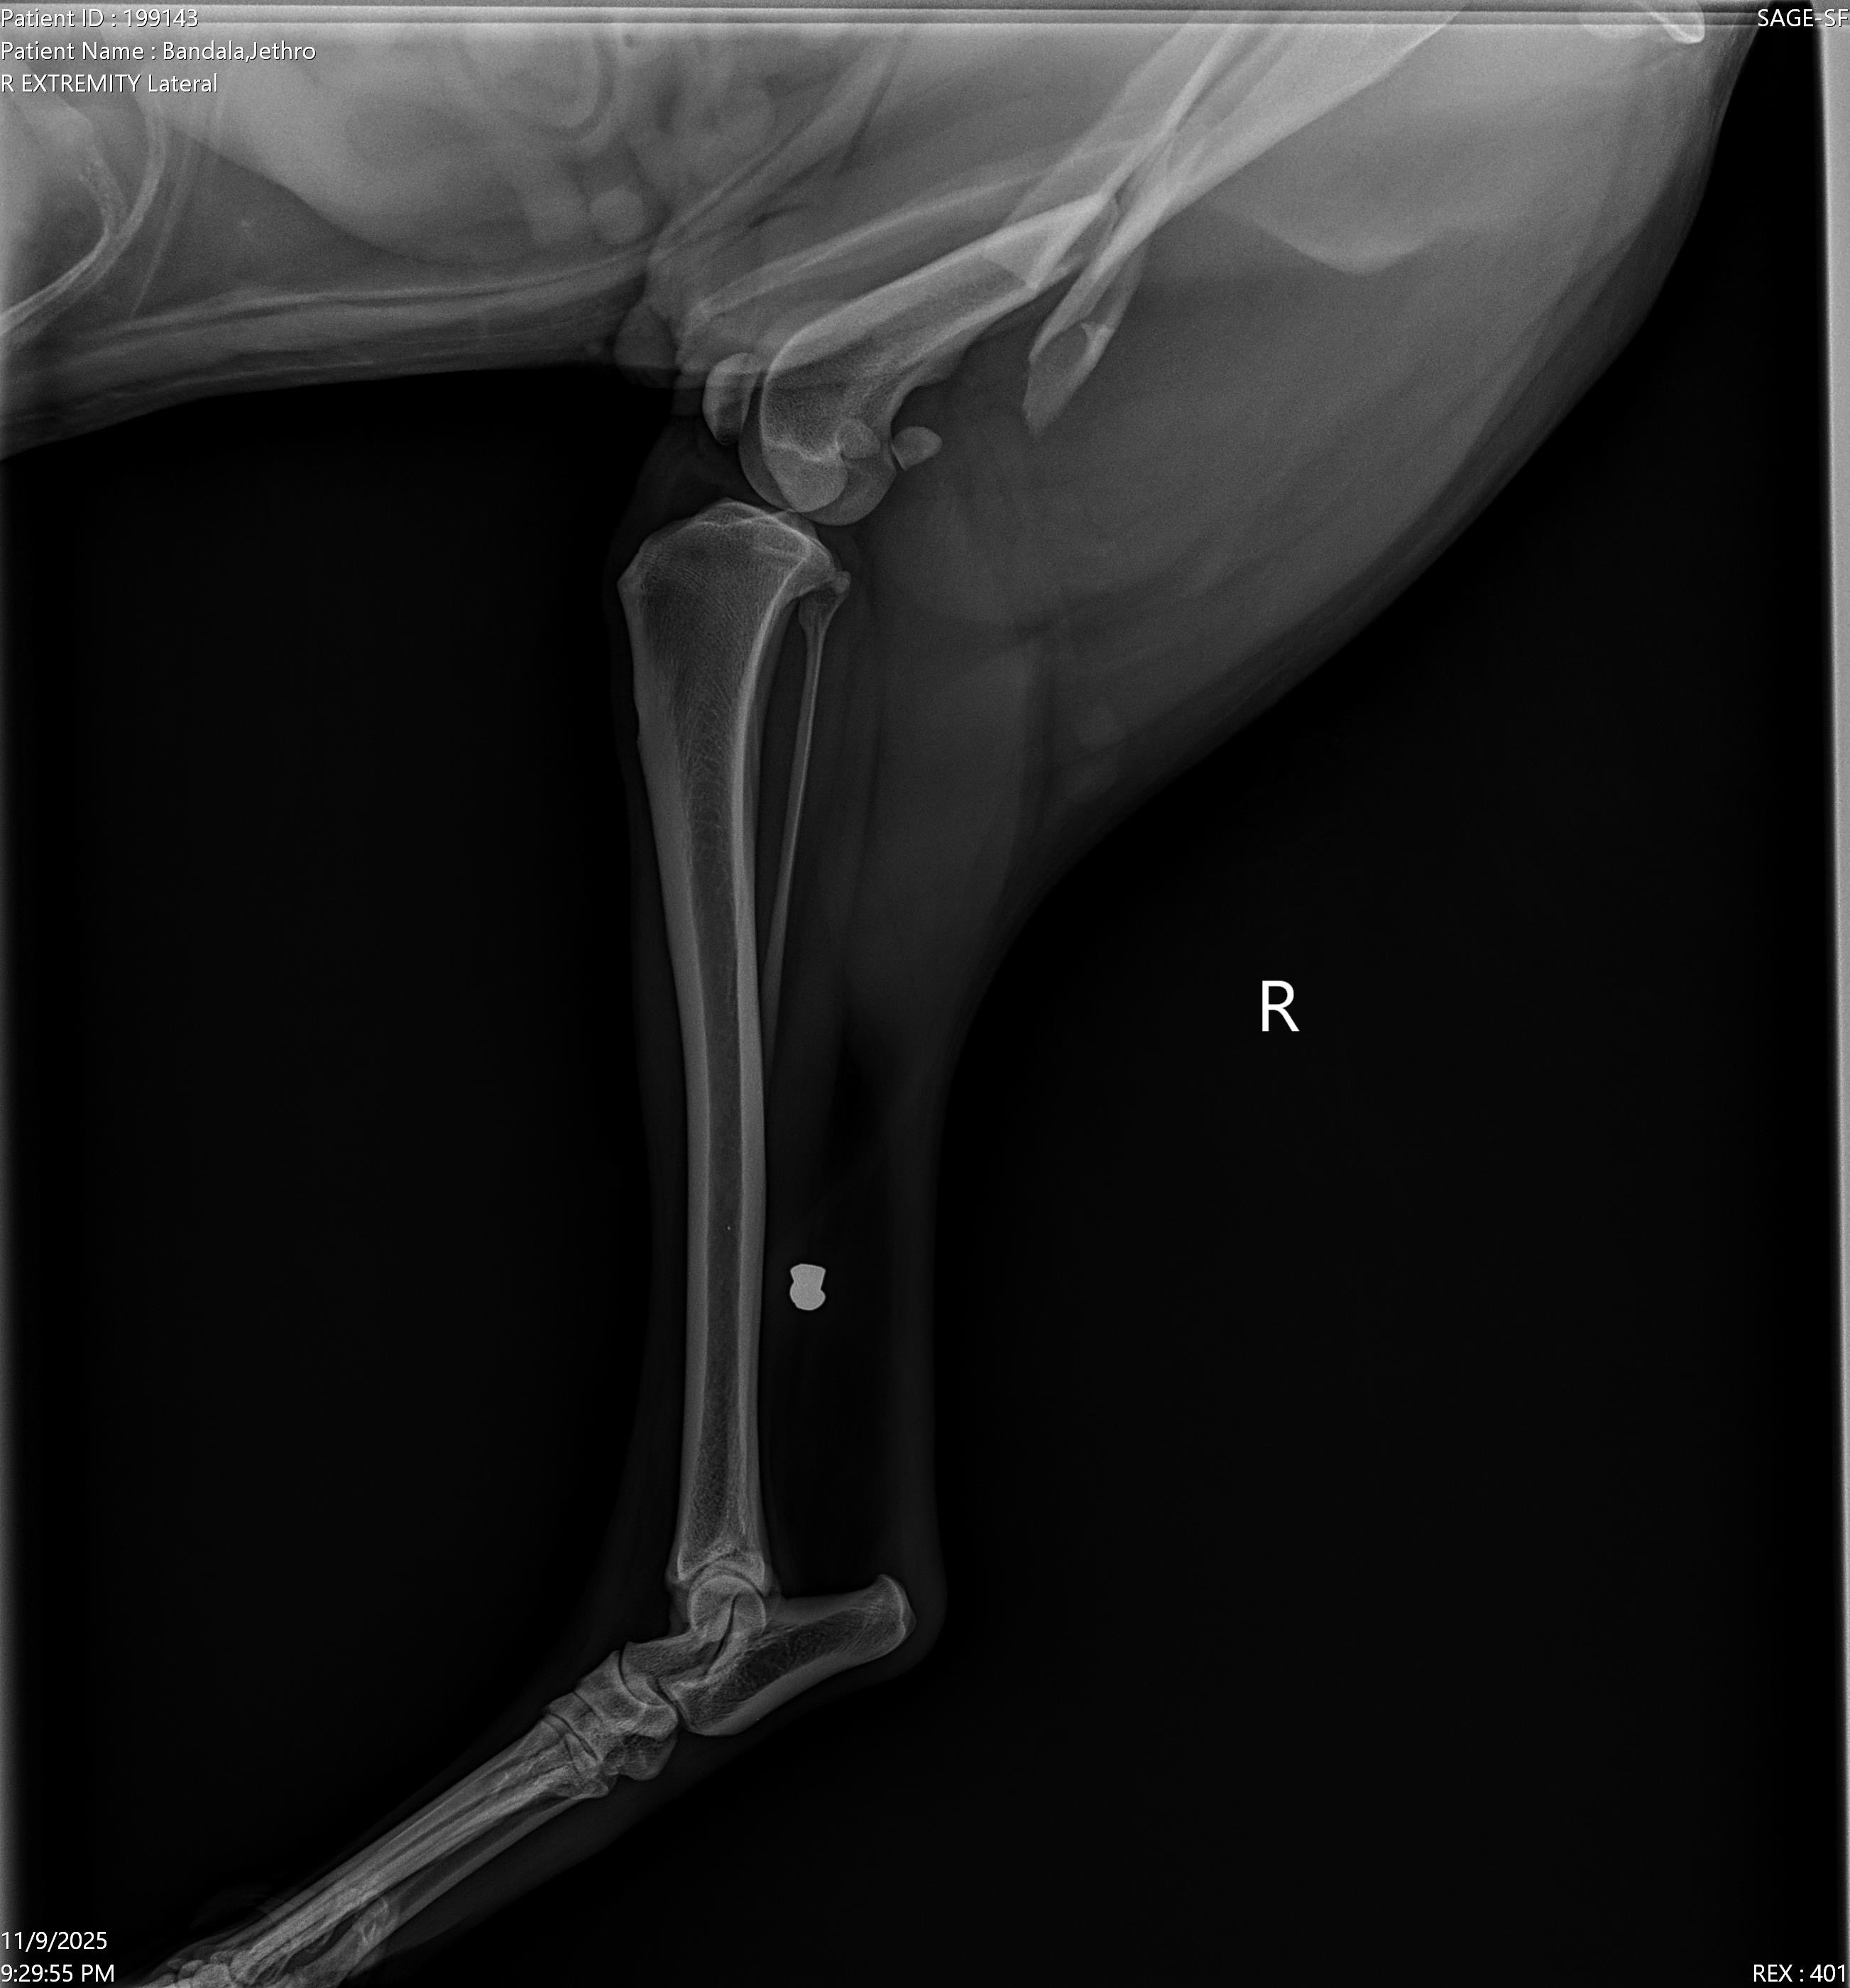

On Sunday, November 9th, Jethro bolted into the street and got hit by a car. His leg is broken all the way through and requires extreme surgery to avoid amputation. Surgery is extremely expensive and Jethro is still so young and has so much life ahead of him. Any amount, even $1, would help so much. Thank you for reading. Pray for the baby.